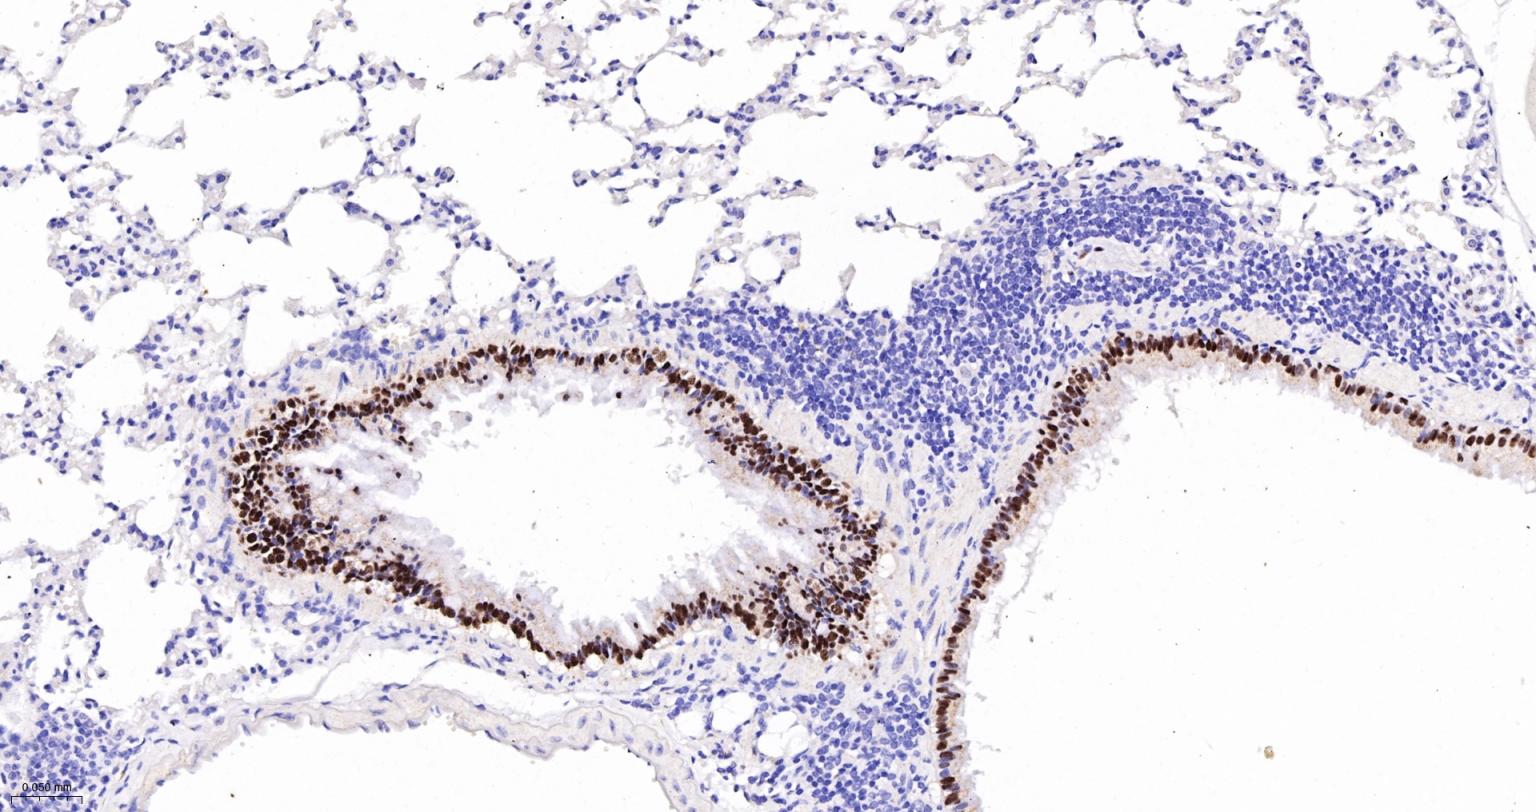

| IHC-P | Human, Mouse, Rat | 1:200-800 | |

| IHC-F | Human, Mouse, Rat | 1:200-800 | |